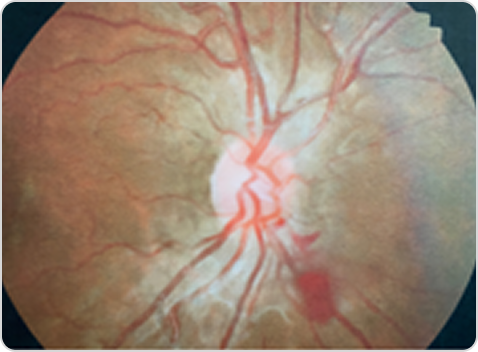

Фабри ауруы кезіндегі тамырлық өзгерістері бар көз түбінің фотосуретіФабри ауруы кезіндегі тамырлық өзгерістері бар көз түбінің фотосуреті

6-сурет. Оң көздің көз түбінің фотосуреті: торқабық тамырларының иректілігі (екіжақты), көру жүйкесі дискінен төменгі-мұрындық квадрантта шынытәрізді денеге аздаған қан құйылу.

Бейімделген дереккөз: Salazar P. Clin Insights Eye Care. 2023;1(1). © 2023 Salazar P. CC BY 4.0.45